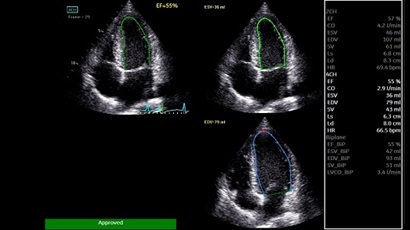

GE VIVID IQ - это передовая портативная система ультразвуковой диагностики, специально разработанная для обеспечения высокого качества образов и мобильности. Благодаря своим компактным размерам и легкому весу, VIVID IQ легко переносится и позволяет проводить УЗИ исследования в различных местах, включая комнаты пациентов, отделения скорой помощи и операционные.

GE VIVID IQ – это ультрасовременный, выполненный в виде ноутбука УЗИ сканер с самым передовым техническим оснащением для проведения диагностических обследований сердечно-сосудистой системы человека. Его особенно оценят бригады скорой помощи из-за малого веса всего 4,5 кг., удобства переноски, а также быстрого выхода из состояния сна для начала работ.

• Передовые технологии, такие как 4D чреспищеводная эхокардиография, ЭКГ, стресс-эхо, внутрисердечная ультразвуковая эхокардиография, тканевый доплер и другие.

• AUTO 2D EF - режим автоматической недопплеровской количественной оценки глобальной сократительной функции ЛЖ (по Simpson).

• AFI - режим цифровой недопплеровской качественной и количественной оценки региональной сократительной функции ЛЖ.